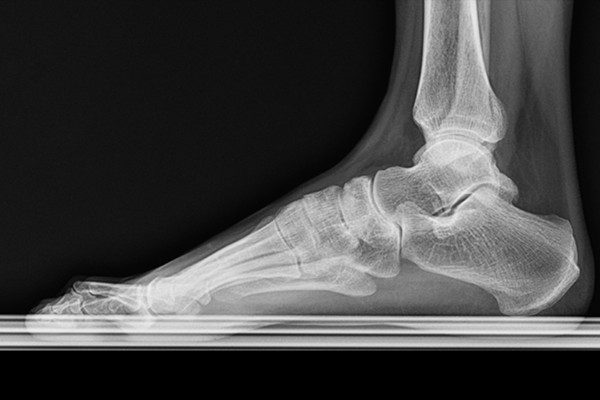

환자분의 발, 발목 상태를 파악하기 위해 X-RAY 검사를 시행하였습니다. 먼저 정상적인 우측발은 거골과 종골 사이 공간이 확인되는 반면,